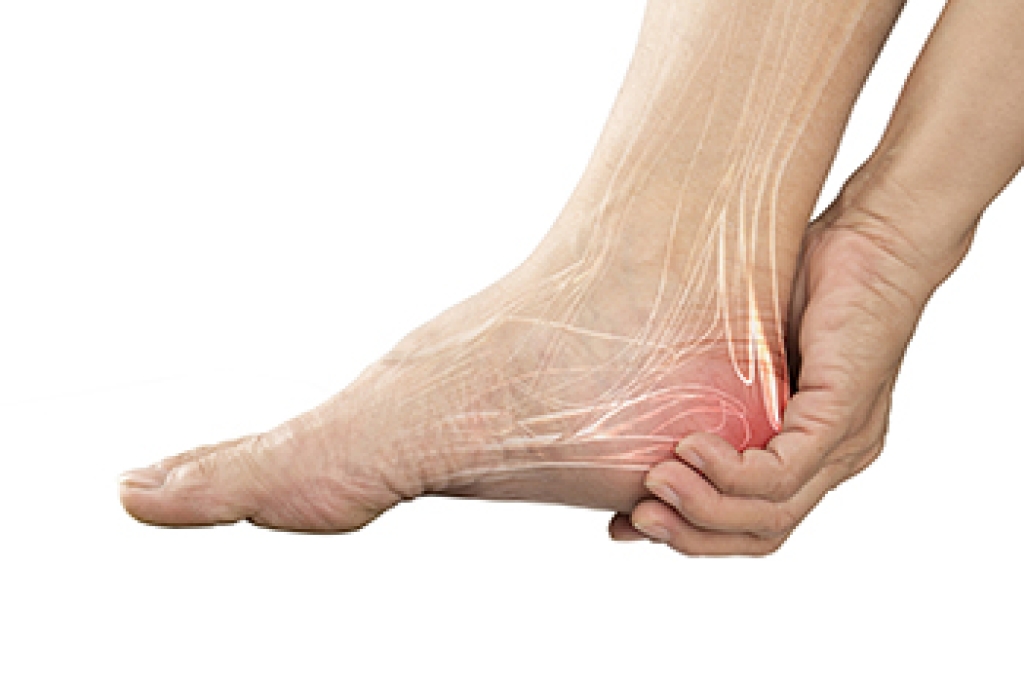

Heel pain in older adults often stems from age-related changes in the feet, including soft tissue degeneration, reduced bone density, and long-standing biomechanical stress. A frequent cause is plantar fasciitis, an inflammatory condition of the plantar fascia that commonly produces sharp pain with the first steps after rest. Heel spurs may develop beneath the calcaneus, or heel bone, and can contribute to additional discomfort. Achilles tendinitis may cause pain at the back of the heel due to overuse or limited flexibility, while arthritis in the rearfoot or midfoot joints can create stiffness and reduced mobility. Seniors are also at increased risk for calcaneal stress fractures, retrocalcaneal bursitis, and heel pad atrophy, which results from thinning of the natural cushioning under the heel. Nerve conditions such as tarsal tunnel syndrome or peripheral neuropathy may cause burning or tingling heel pain. If you have ongoing heel pain, it is suggested that you make an appointment with a podiatrist to determine the underlying cause and select appropriate treatment.

Heel pain is often associated with plantar fasciitis. The plantar fascia is a band of tissues that extends along the bottom of the foot. A rip or tear in this ligament can cause inflammation of the tissue.

Achilles tendonitis is another cause of heel pain. Inflammation of the Achilles tendon will cause pain from fractures and muscle tearing. Lack of flexibility is also another symptom.

Heel spurs are another cause of pain. When the tissues of the plantar fascia undergo a great deal of stress, it can lead to ligament separation from the heel bone, causing heel spurs.

Heel pain should be treated as soon as possible for immediate results. Keeping your feet in a stress-free environment will help. If you suffer from Achilles tendonitis or plantar fasciitis, applying ice will reduce the swelling. Stretching before an exercise like running will help the muscles. Using all these tips will help make heel pain a condition of the past.